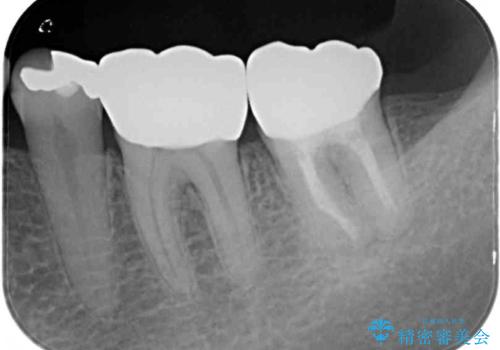

上顎の奥歯は神経にまで虫歯が及んでいる可能性が高かったため、抜髄や断髄の可能性を考慮しながら処置を進め、セラミッククラウンにて補綴することとしました。

上の奥歯は一部神経を取り除くこととなりましたが、残った神経は正常な状態を保つことができました。